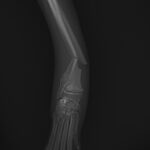

5ヶ月齢の小型犬がソファーからジャンプしたのちに橈骨骨折をしたとの事で、かかりつけ医より紹介受診されました。橈骨は遠位で階段状斜骨折を呈していました。遠位3穴にデザインされたストレートの1.5 Locking Plateをメインとし、橈骨の内側面からOrthogonal Plateにより骨接合術を行いました。しばらくは安静が必要です。